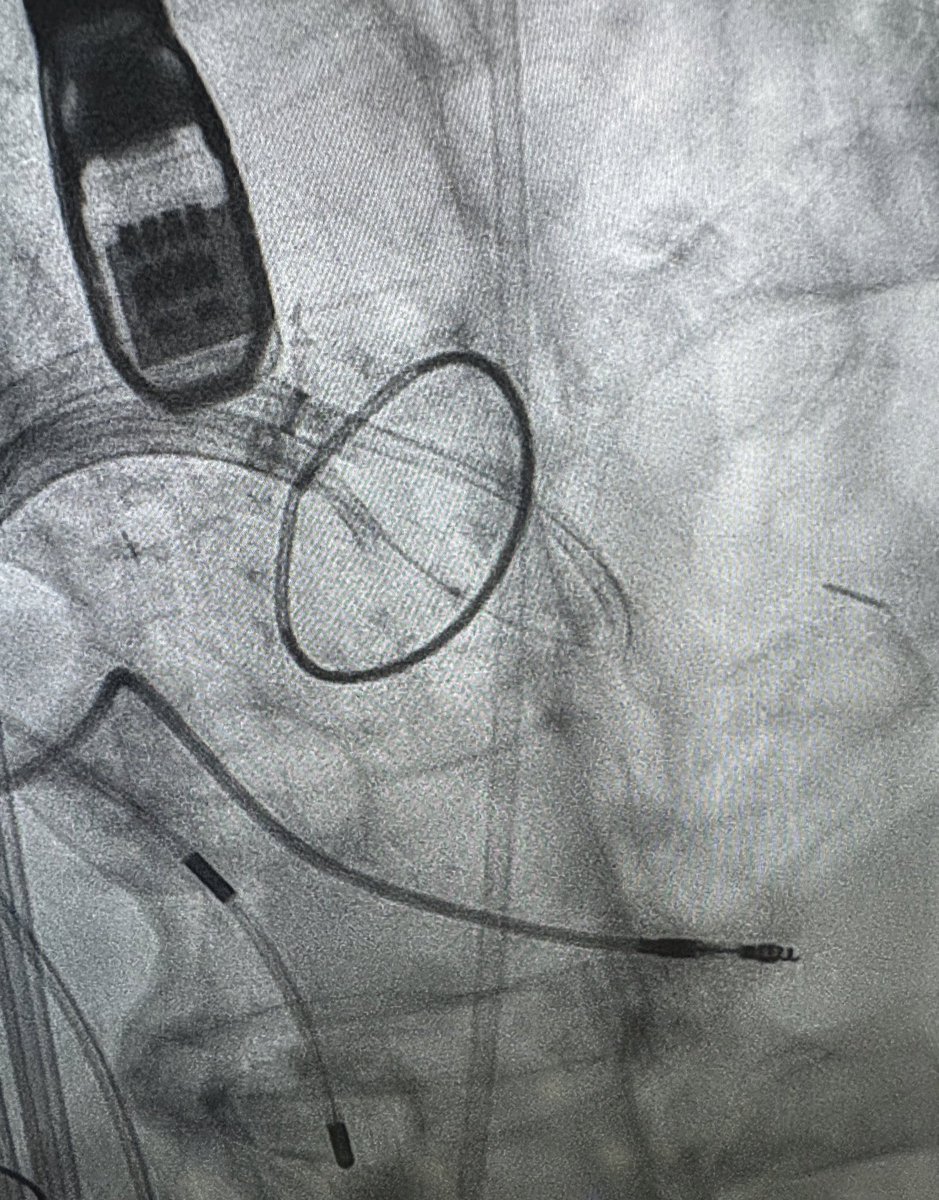

β€œV” shaped split of the anterior mitral leaflet after LAMPOON before valve-in-ring

Laceration of the Anterior Mitral Leaflet #LAMPOON and #TMVR Valve-in-Ring for mitral stenosis in patient with 2 previous heart surgeries. Electrosurgery and complex structural heart intervention things you only find at few leading valve programs in the country.